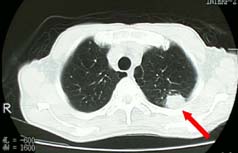

ヘリカルCTにより、3〜5mmの肺がんも発見しています。 肺がんは、CTでなければ、小さいがんは発見しにくいので、 特に、喫煙者には必ずCT検査を勧めます。 |